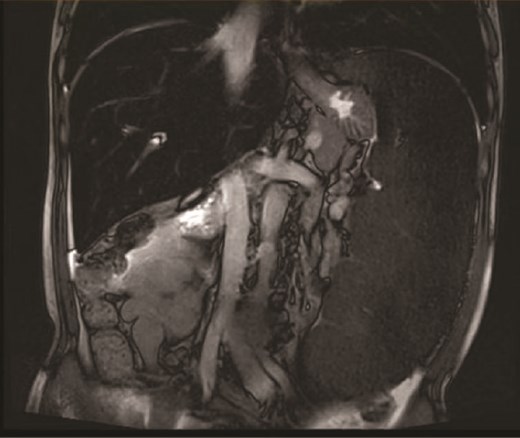

On the 19 August 2024, a 53-year-old man reported to our hospital complaining of “fatigue, jaundice, and abdominal discomfort for 10 years.” His hemolytic jaundice had been present for almost a decade. A family history of hereditary hemolytic jaundice was identified. His daughter and father both experienced similar ailments. Physical evaluation revealed that the skin and sclera were both stained by moderate yellowness. The left abdomen was full, and the spleen was hard and immovable, located 15 cm below the costal border. A computed tomography scan revealed that the spleen was 27.1 cm in length, 7.1 cm in thickness, and located 17.0 cm below the costal border (Figs. 1 and 2). The gallbladder measured 12.0 × 3.2 cm and contained several stones.